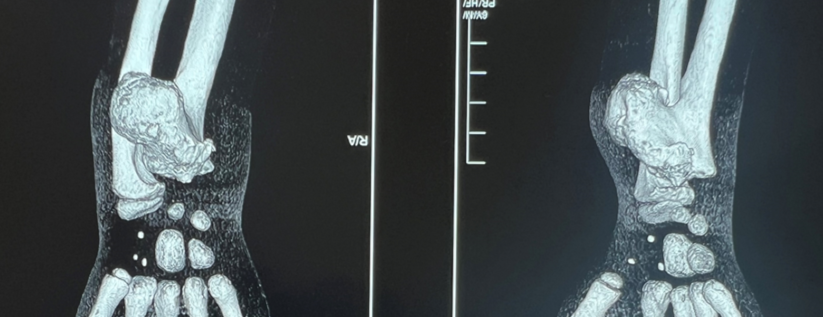

«У Демида диагностирована остеохондрома дистального метаэпифиза правой локтевой кости, опухоль размером 4×5 см — что сопоставимо с объёмом предплечья ребенка. Часто такое новообразование может появляться в зоне роста кости, и в данном случае затрагивает и зону роста, и эпифиз — и вследствие этого локтевая кость деформирована и отстаёт в размерах.

Хирургическое вмешательство было направлено на полное удаление данного образования.

Новообразование располагалось вблизи локтевой артерии и локтевого нерва, и необходимо было действовать максимально аккуратно, не повреждая мягкие ткани, сосудисто-нервный пучок. В послеоперационном периоде ребенок хорошо себя чувствует, движения в лучезапястном суставе — в полном объёме, поэтому реконструктивных вмешательств на предплечье на данный момент не планируется», — объясняет врач-травматолог-ортопед Дастанбек Абдикапаров.